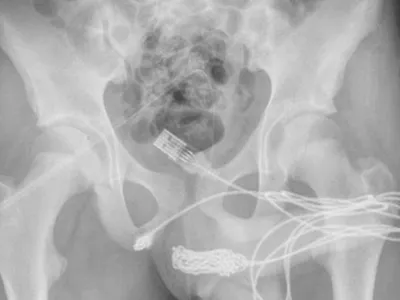

Un tânăr a vrut să-și măsoare "virilitatea" din interiorul corpului cu un cablu USB. A rămas blocat

Un tânăr din Marea Britanie a vrut să afle cât de mare este penisul său în interior, așa că a decis să folosească un cablu USB pentru a-l măsura - nu s-a terminat deloc bine pentru el. A ajuns la spital.